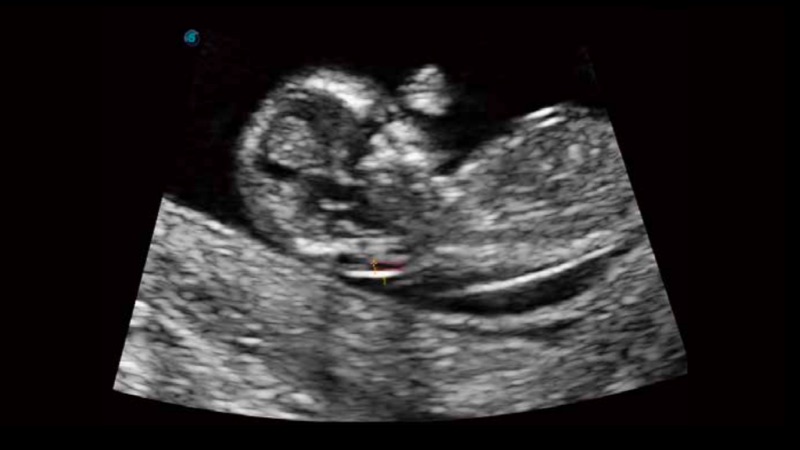

Based on a big data dependable deep learning algorithm, S-Fetus is a brilliant one-step solution for automatic standard plane acquisition and measurement. With just one click, common fetal biometry results are obtained with high intelligence, accuracy and efficiency, aiming for an unprecedented ease during operation.

Less keystroke required while achieving more sensitive and advanced automated common fetal biometry.